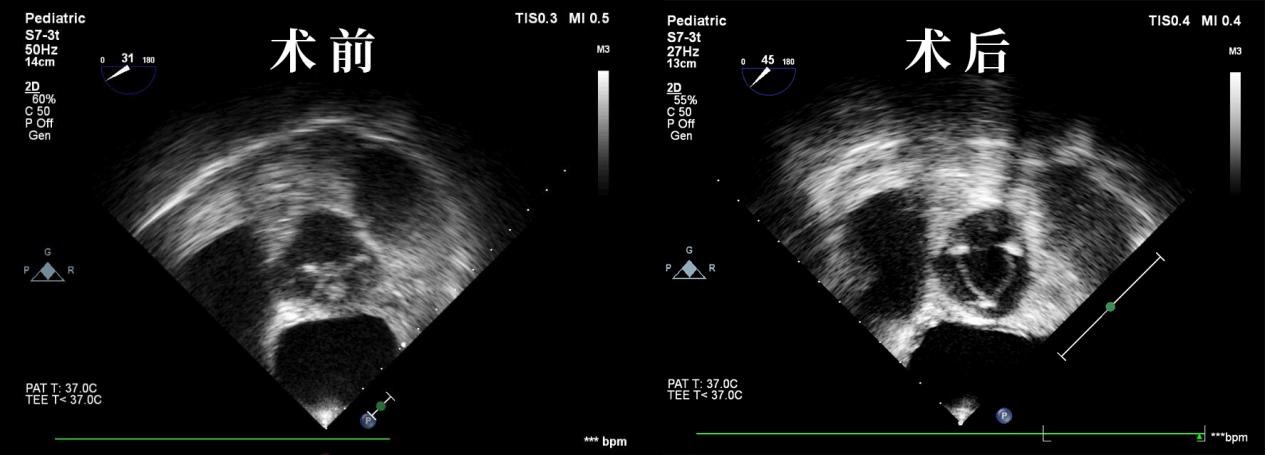

干瓣很牛亚心总医院成功完成华中地区首例主动脉瓣干瓣植入术

图片尺寸1265x455